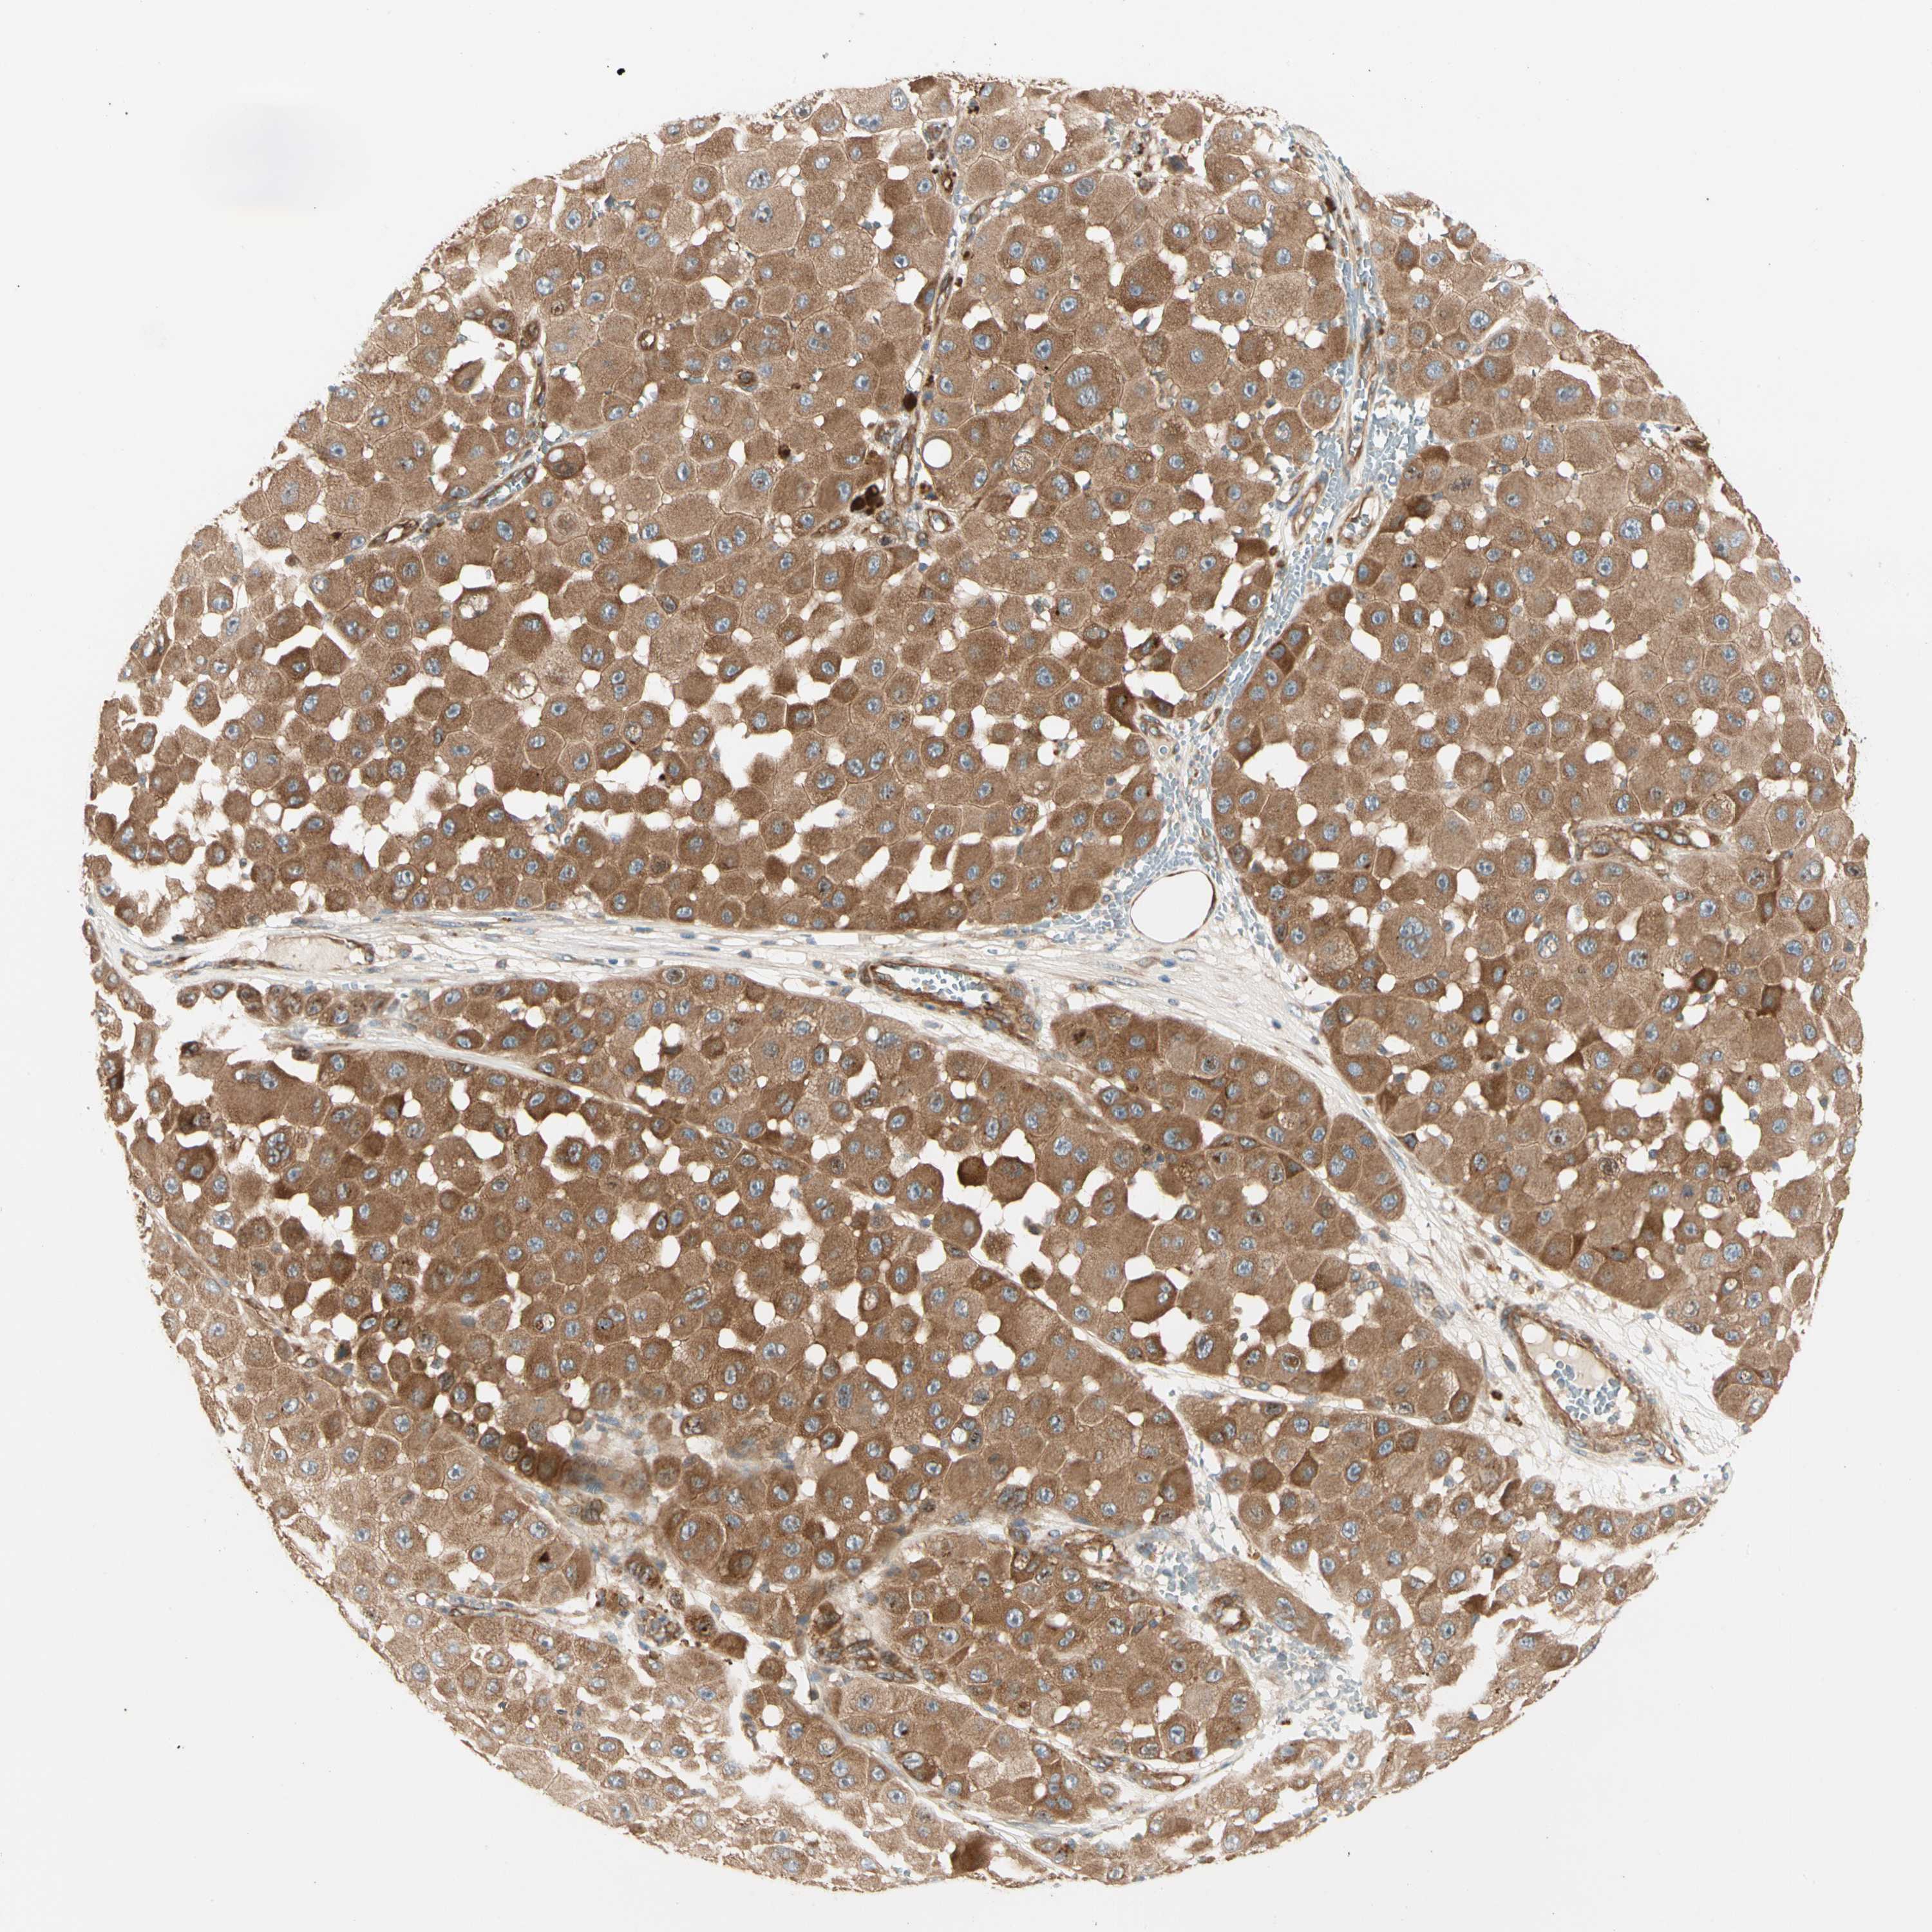

MELANOMA - Protein expressioni

A mouse-over function shows sample information and annotation data. Click on an image to view it in a full screen mode. Samples can be filtered based on level of antibody staining by selecting one or several of the following categories: high, medium, low and not detected. The assay and annotation is described here.

Note that samples used for immunohistochemistry by the Human Protein Atlas do not correspond to samples in the TCGA dataset.

Antibody stainingi

Antibody staining in the annotated cell types in the current human tissue is reported as not detected, low, medium, or high, based on conventional immunohistochemistry profiling in selected tissues. This score is based on the combination of the staining intensity and fraction of stained cells.

Each image is clickable and will lead to virtual microscopy that enables deeper exploration of all samples and also displays staining intensity scores, fraction scores and subcellular localization as well as patient and tissue information for each sample.

Antibody HPA007459

Antibody CAB008666

Staining

High

Medium

Low

Not detected

Intensity

Strong

Moderate

Weak

Negative

Quantity

>75%

75%-25%

<25%

None

Location

Nuclear

Cytoplasmic/membranous

Cytoplasmic/membranous,nuclear

Malignant melanoma, NOS

Malignant melanoma, Metastatic site